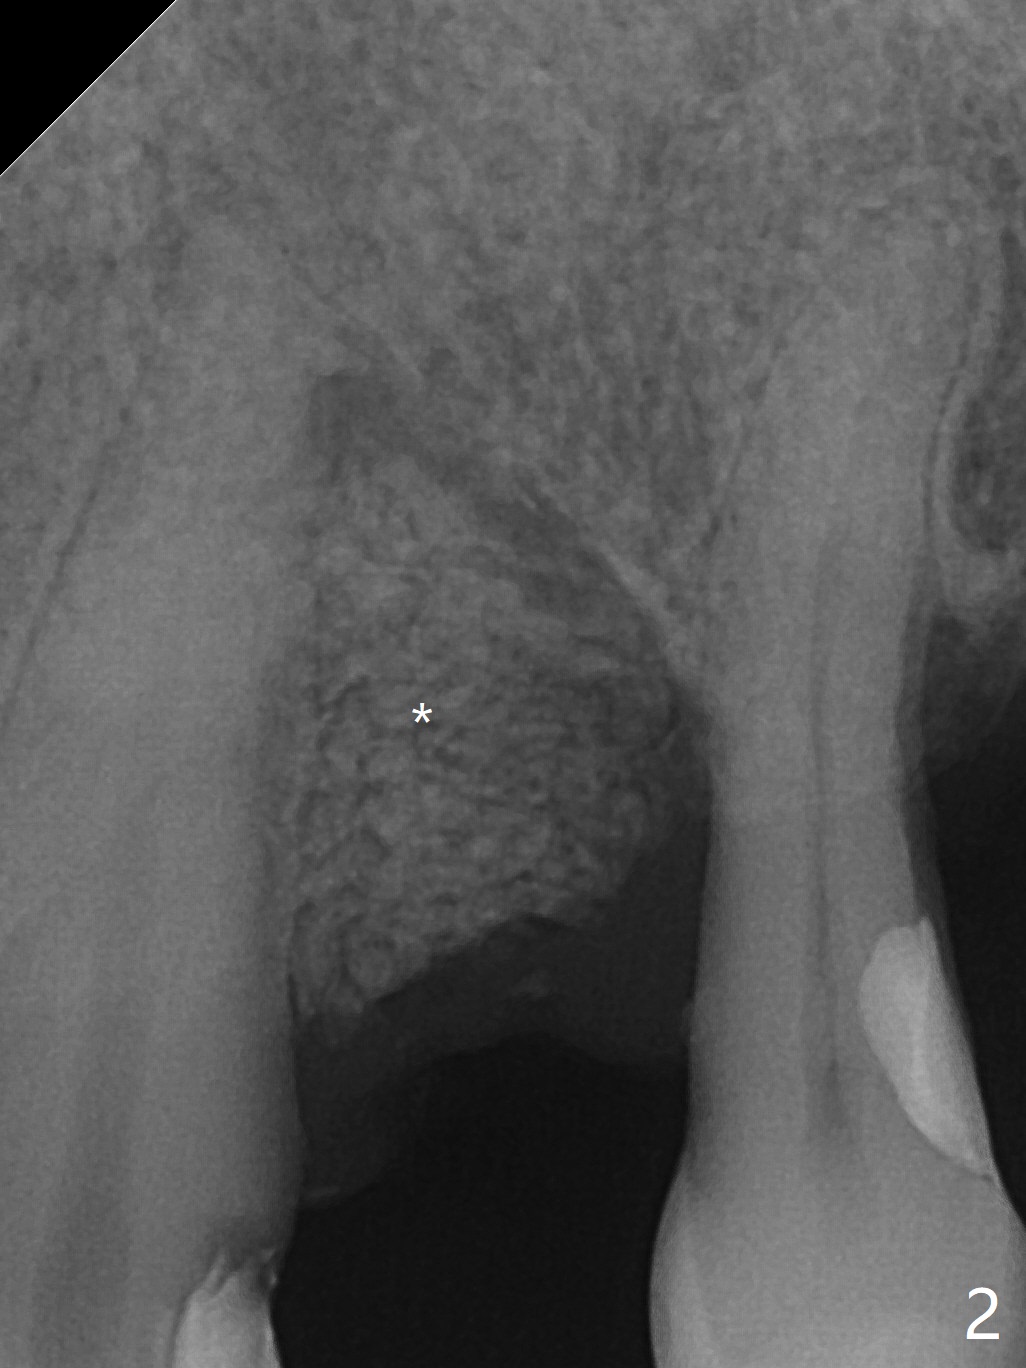

A 55-year-old man has been our patient intermittently for the last 15 years. Before removal of the tooth #12 with loss of the buccal plate (Fig.1), he requests bone graft for the health (strength) of the neighboring teeth (Fig.2 *). To keep the 6-month membrane in place longer, periodontal glue is used after suturing (Fig.3 (blue)). There is buccal collapse 2 months post socket preservation (Fig.4,5). Titanium mesh or Cytoplast should have been placed.